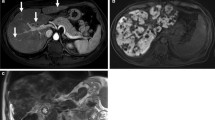

Sinusoidal obstruction syndrome. A 62-year-old man with colorectal liver metastases. (a) Prior to chemotherapy axial hepatobiliary phase image shows a liver metastasis in segment VIII and homogeneous enhancement of the liver parenchyma. (b) After four cycles of capecitabine and oxaliplatin, the liver metastasis decreased in size. The liver parenchyma shows a reticular hypointense pattern on hepatobiliary phase corresponding to parenchymal changes due to sinusoidal obstruction syndrome